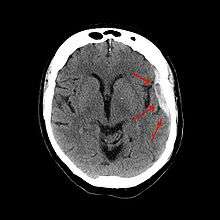

A subdural hematoma demonstrated by CT.

It is important that a person receive medical assessment, including a complete neurological examination, after any head trauma. A CT scan or MRI scan will usually detect significant subdural hematomas.

Subdural hematomas occur most often around the tops and sides of the frontal and parietal lobes.[3][8] They also occur in the posterior cranial fossa, and near the falx cerebri and tentorium cerebelli.[3] Unlike epidural hematomas, which cannot expand past the sutures of the skull, subdural hematomas can expand along the inside of the skull, creating a concave shape that follows the curve of the brain, stopping only at the dural reflections like the tentorium cerebelli and falx cerebri.

On a CT scan, subdural hematomas are classically crescent-shaped, with a concave surface away from the skull. However, they can have a convex appearance, especially in the early stage of bleeding. This may cause difficulty in distinguishing between subdural and epidural hemorrhages. A more reliable indicator of subdural hemorrhage is its involvement of a larger portion of the cerebral hemisphere since it can cross suture lines, unlike an epidural hemorrhage. Subdural blood can also be seen as a layering density along the tentorium cerebelli. This can be a chronic, stable process, since the feeding system is low-pressure. In such cases, subtle signs of bleeding such as effacement of sulci or medial displacement of the junction between gray matter and white matter may be apparent. A chronic bleed can be the same density as brain tissue (called isodense to brain), meaning that it will show up on CT scan as the same shade as brain tissue, potentially obscuring the finding.